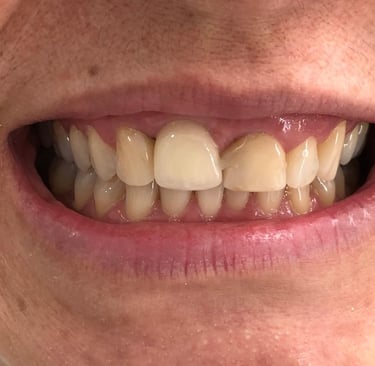

Coroas em Dissilicato de Lítio

Todos os caso a seguir estão associadas a clareamento dentário

Antes

Depois